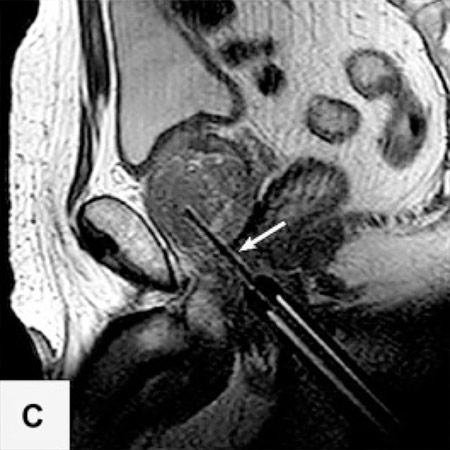

Die Probleme der Fusionsbiopsie und der Unsichtbarkeit von Krebsherden im Ultraschall lassen sich auf elegante Weise vermeiden, wenn die Biopsie direkt MRT-gesteuert im Kernspintomographen selbst ausgeführt wird.

In der Vitus Privatklinik nutzen wir diese Möglichkeit der präzisen, direkt durch MRT-Bilder gesteuerten Biopsie. Dazu wird die Biopsienadel entweder manuell oder mit einem Soteria Biopsie-Roboter in den verdächtigen Herd gesteuert, unter direkter MRT-Kontrolle. Dies ermöglicht es, mit hoher Präzision, die Biopsienadel direkt in den verdächtigen Herd in der Prostata zu steuern. Dort angekommen kann die Biopsie im MRT direkt verfolgt werden, und nach der Probenentnahme durch die Darstellung des Stichkanales überprüft werden, ob der Herd getroffen wurde. Auf diese Weise können auch kleine Karzinomherde mit hoher Sicherheit biopsiert werden2.